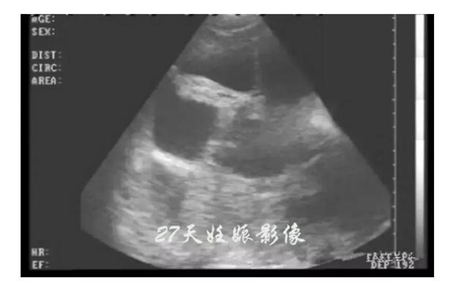

20天孕期左右的母猪,即可进行B超测孕,但由于羊水太少,图像不好判断,准确度也会因检测人员经验因素有所影响,容易造成误判,而且检查时间长,耗费人力。

45天孕期后的母猪测孕,羊水开始吸收并减少,小猪开始成型,图像复杂同样不好判断。同时,母猪的情期平均是21天,如果不能在第21天至42天之内确定是否怀孕,那意味着猪场又要再养一个周期才能配种,造成极大的浪费。